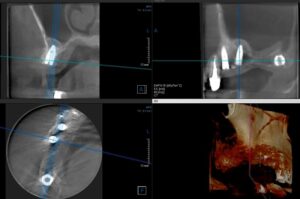

今年の二回目のインプラント埋入手術をしました。 上の奥歯が四本無くて、そこに三本のインプラントを埋めました。下のレントゲン写真はCTの写真です。左下が水平の断面で上の二つが前からと横からの垂直断面です。 一番前(写真では右上側の写真の一番左 […] 本文を読む